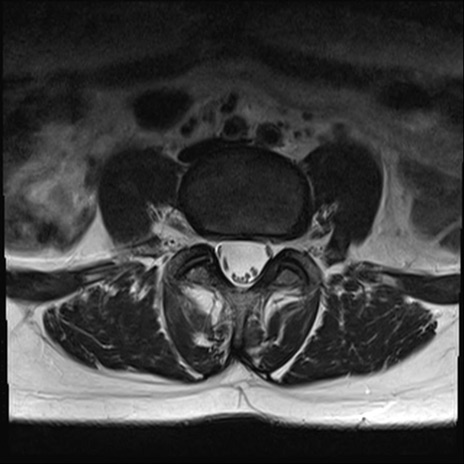

【整形】TIPS症例4 腰椎MRI T2WI(横断像)

横断像と矢状断像